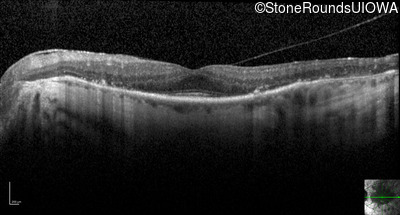

Optical Coherence Tomography - Left - 20/25 -2 sc

Exemplar / OCT Stack